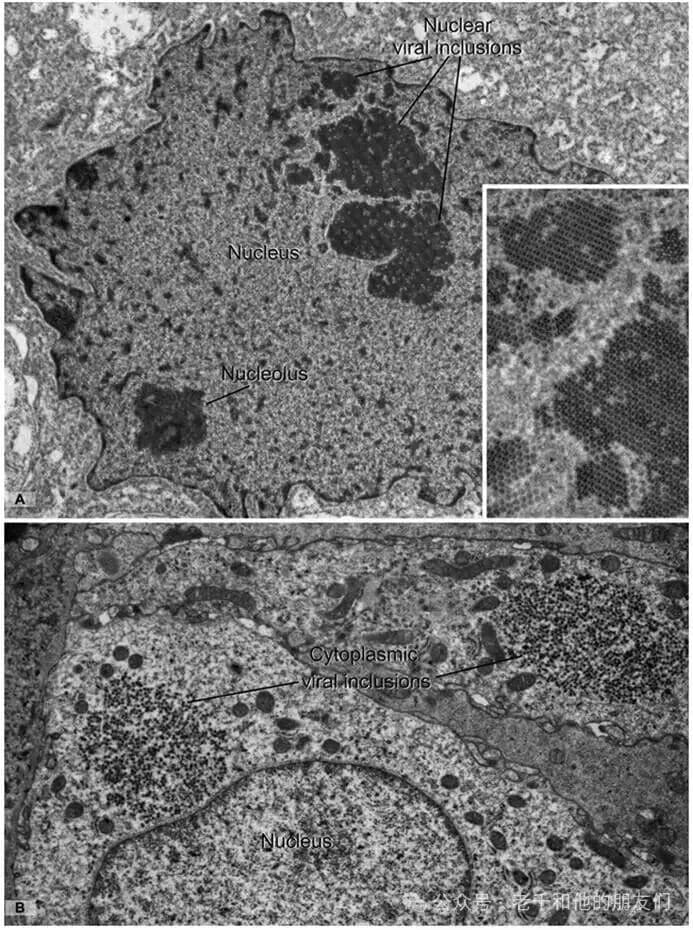

图 12 病毒包涵体的超微结构(多瘤病毒感染)

病毒颗粒体积小(20-300nm),需电子显微镜检测,部分病毒感染后可在细胞内形成聚集体(病毒包涵体)。

样本为肾移植患者肾活检组织(肾小管细胞多瘤病毒感染):A 图(核内)、B 图(胞质内):病毒包涵体由 30-45nm 的球形病毒颗粒组成,呈特征性类晶体排列(A 图插图高倍清晰显示),核内包涵体可与核仁明确区分(结构差异显著)。此外,巨细胞病毒(疱疹病毒科)可引起核质联合包涵体,常见于免疫抑制人群(移植受者、艾滋病患者)。放大倍数:A、B 图 ×12,000;A 图插图 ×35,000